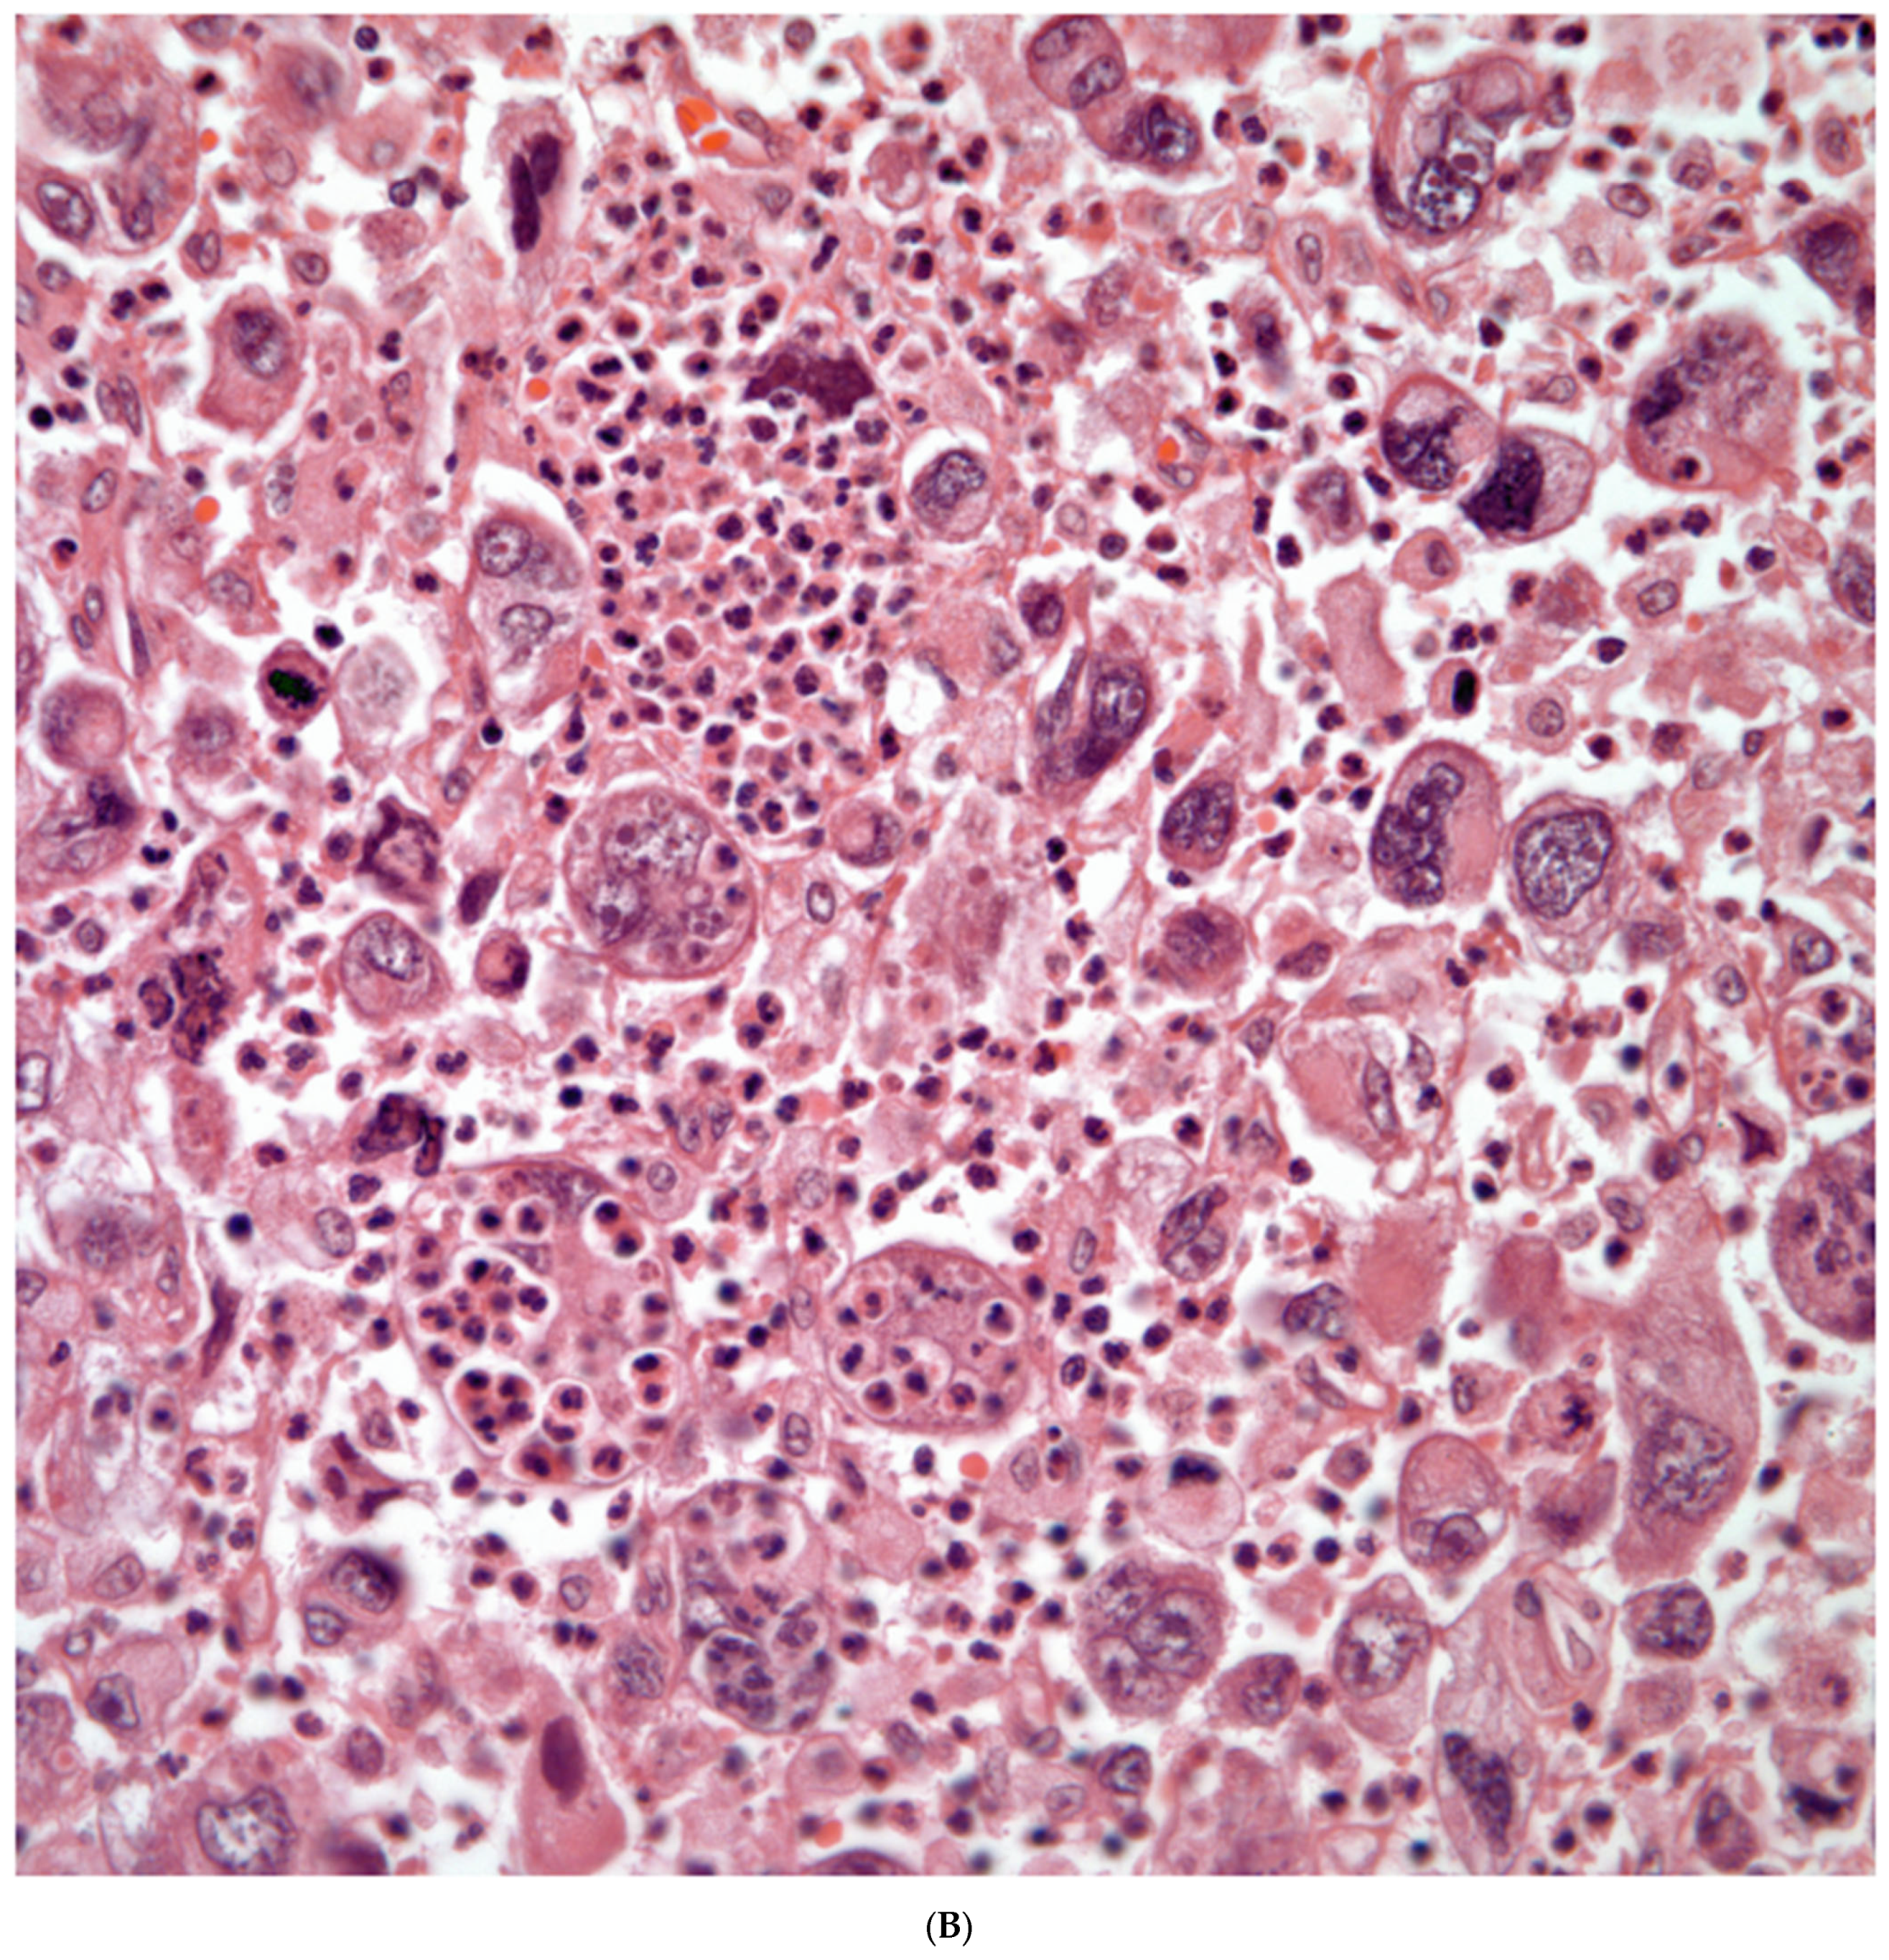

Giant Cell Carcinomas: These tumors may show predominantly a neoplastic cellular proliferation composed exclusively of multinucleated giant cells or a predominantly giant cell carcinoma (Figure 5A,B) or associated with a conventional non-small cell carcinoma like adenocarcinoma or squamous cell carcinoma. The giant cell carcinoma may show giant cells of the syncytiotrophoblastic, osteoclastic, or null cell type. The giant cell carcinomas of the null cell type characteristically show a prominent inflammatory background and giant cells engulfing inflammatory cells (emperipolesis) (Figure 6A,B). The tumors composed of osteoclast-like giant cells show giant cells like those described in bone tumors (Figure 7A,B).

Figure 6.

(A) Giant cell carcinoma, null cell type, note the inflammatory background; (B) Malignant giant cells with inflammatory cells and focal emperipolesis.